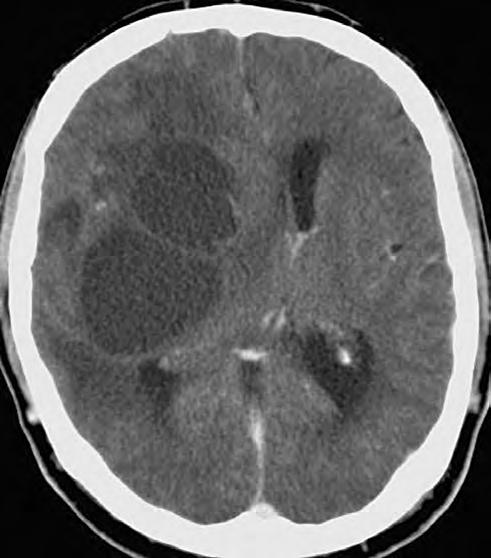

Obr. 1.3 CT pokročilého astrocytomu III.stupně, který je nápadný rozsahem své velikosti, expanzivním chováním a kolaterálním edémem.

Expanzivní ložisko vCNS může být někdy způsobeno benigním patologickým procesem (abscesem, kavernomem, meningeomem), ale může jít také ometastázu známého nebo doposud ukrytého tumoru, viz obr. 1.4 a1.5. Do mozku často metastazují následující tumory: bronchogenní karcinom, obzvláště jeho malobuněčná varianta, karcinomy prsu aledvin. V80 %případů jsou tyto metastázy uloženy supratentoriálně.